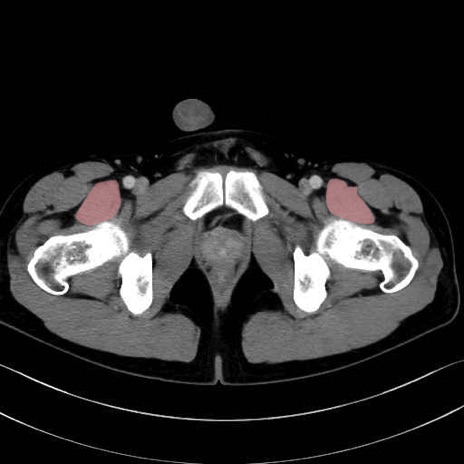

腸骨筋 (Iliacus)

内閉鎖筋 (Obturator internus)